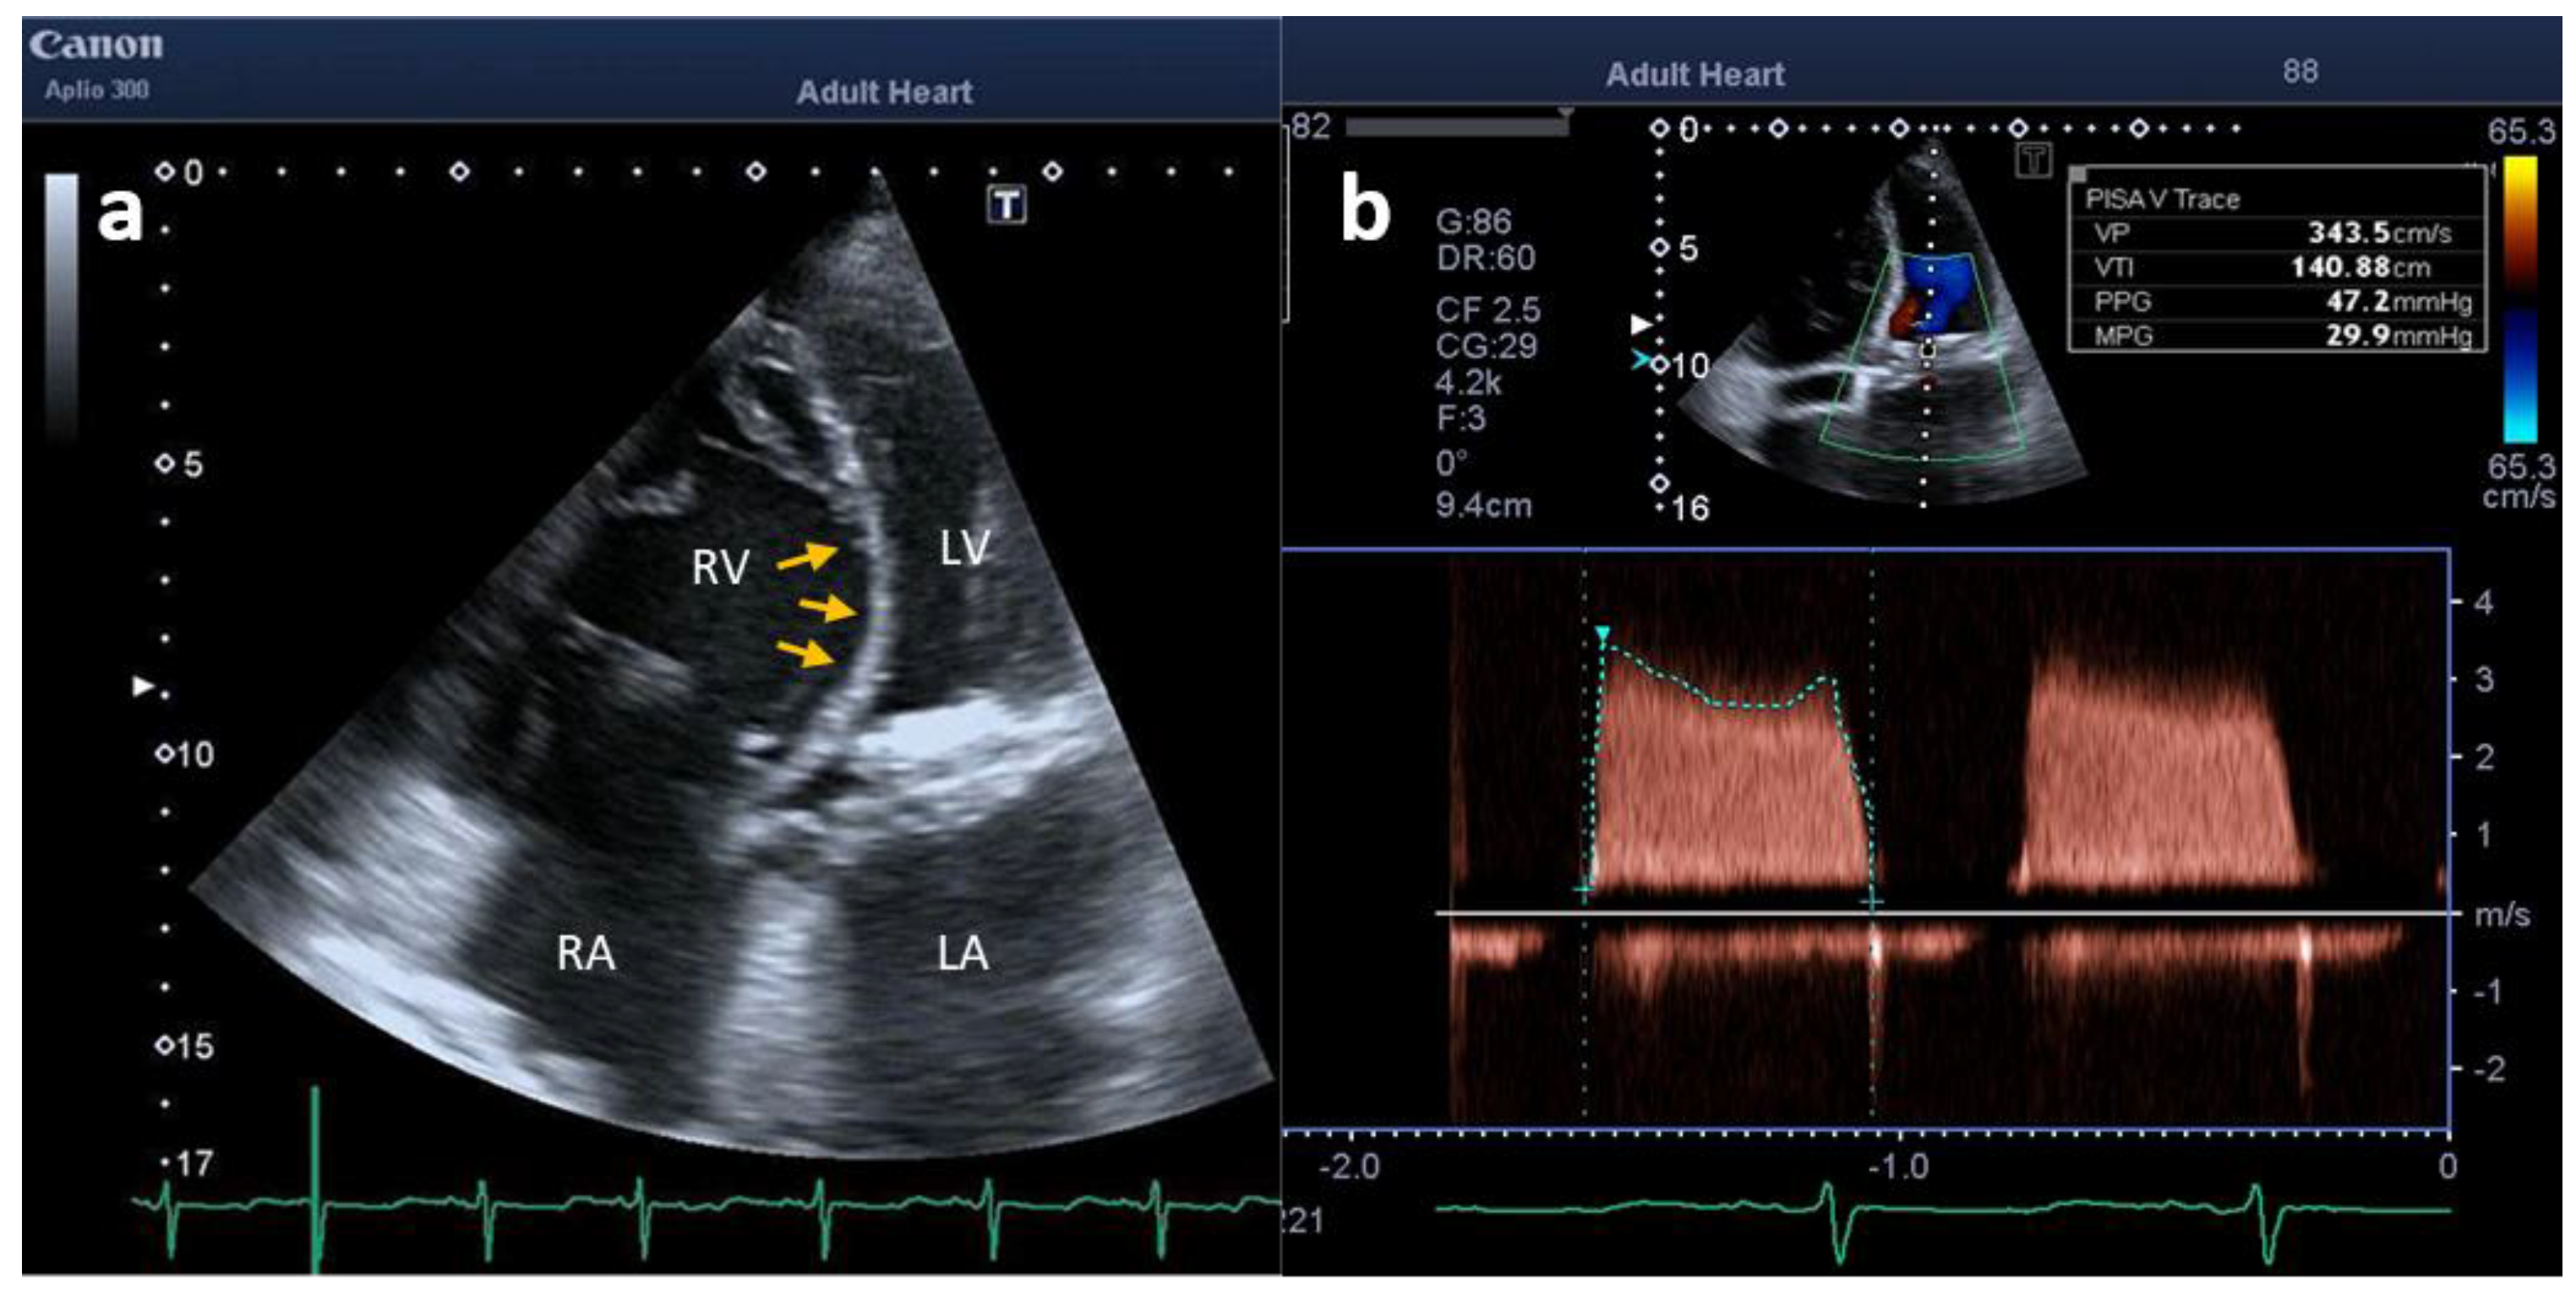

2. Case Description